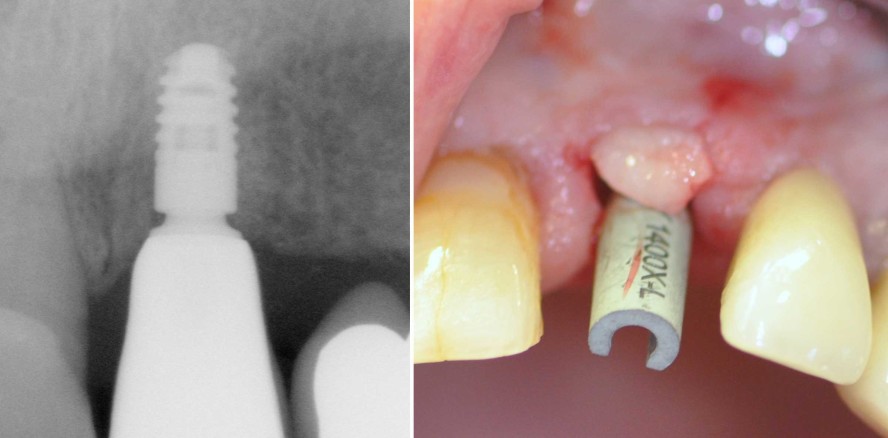

Ausgehend vom initial bestehenden Defekt konnte das Implantat in der korrekten Position eingebracht werden (Abb. 12). Die postoperative radiologische Kontrolle nach Implantation zeigt das gut positionierte Implantat (Abb. 13). Drei Monate nach der Implantatinsertion erfolgt dann das volldigitale Herstellen der einteiligen okklusal verschraubten Abutmentkrone nach dem One-Abutment-One-Time-Prinzip (Abb. 14). Abbildung 15 zeigt die finale Arbeit mit optimalen periimplantären Hart- und Weichgewebebedingungen. Eine weitere Röntgenkontrolle zehn Monate nach Einsetzen der finalen Krone zeigt das stabile Knochenniveau um das Implantat 21 (Abb. 16).